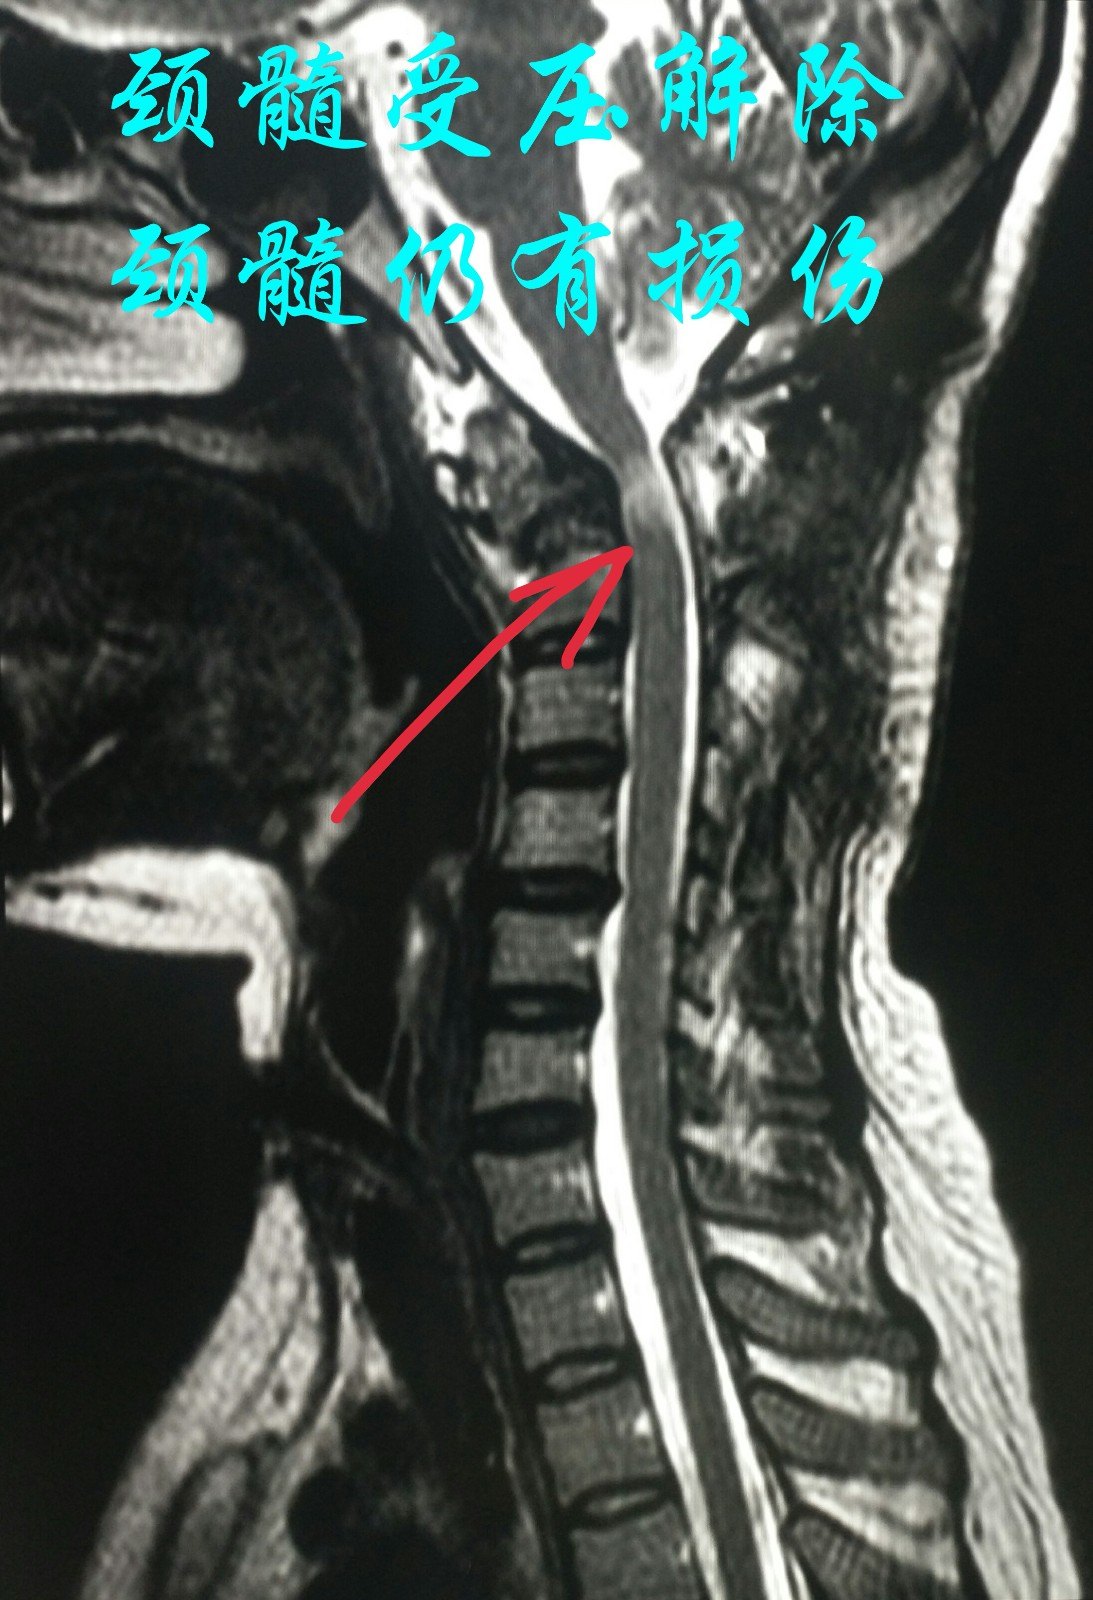

颈椎磁共振提示颈髓受压解除

治疗一月后